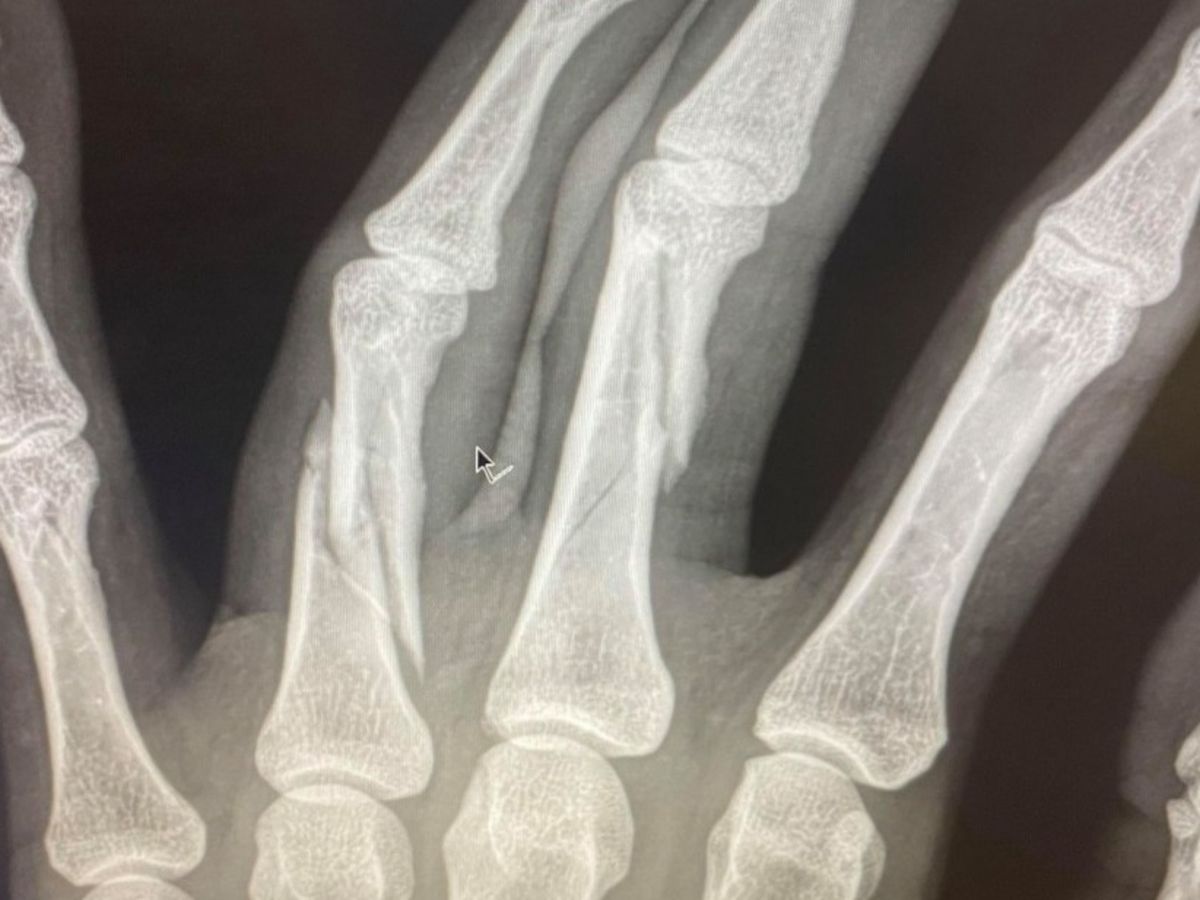

On October 7th, I was in a car crash with a semi-truck, causing multiple injuries, the most serious of which being 3 broken fingers. The injuries to my hand require surgery which will take place on October 19. Altogether, I will be in recovery from 3 - 4 months, while also recovering from an MCL tear.

Tuesday's surgery was a success. Once the surgeon began, he quickly realized the damage was more extensive than the x-rays showed. What was supposed to be a 2-hour surgery ended up taking over 6 hours. They had to reconstruct my middle and ring finger, with 11 screws and 2 pins in my pinky finger.